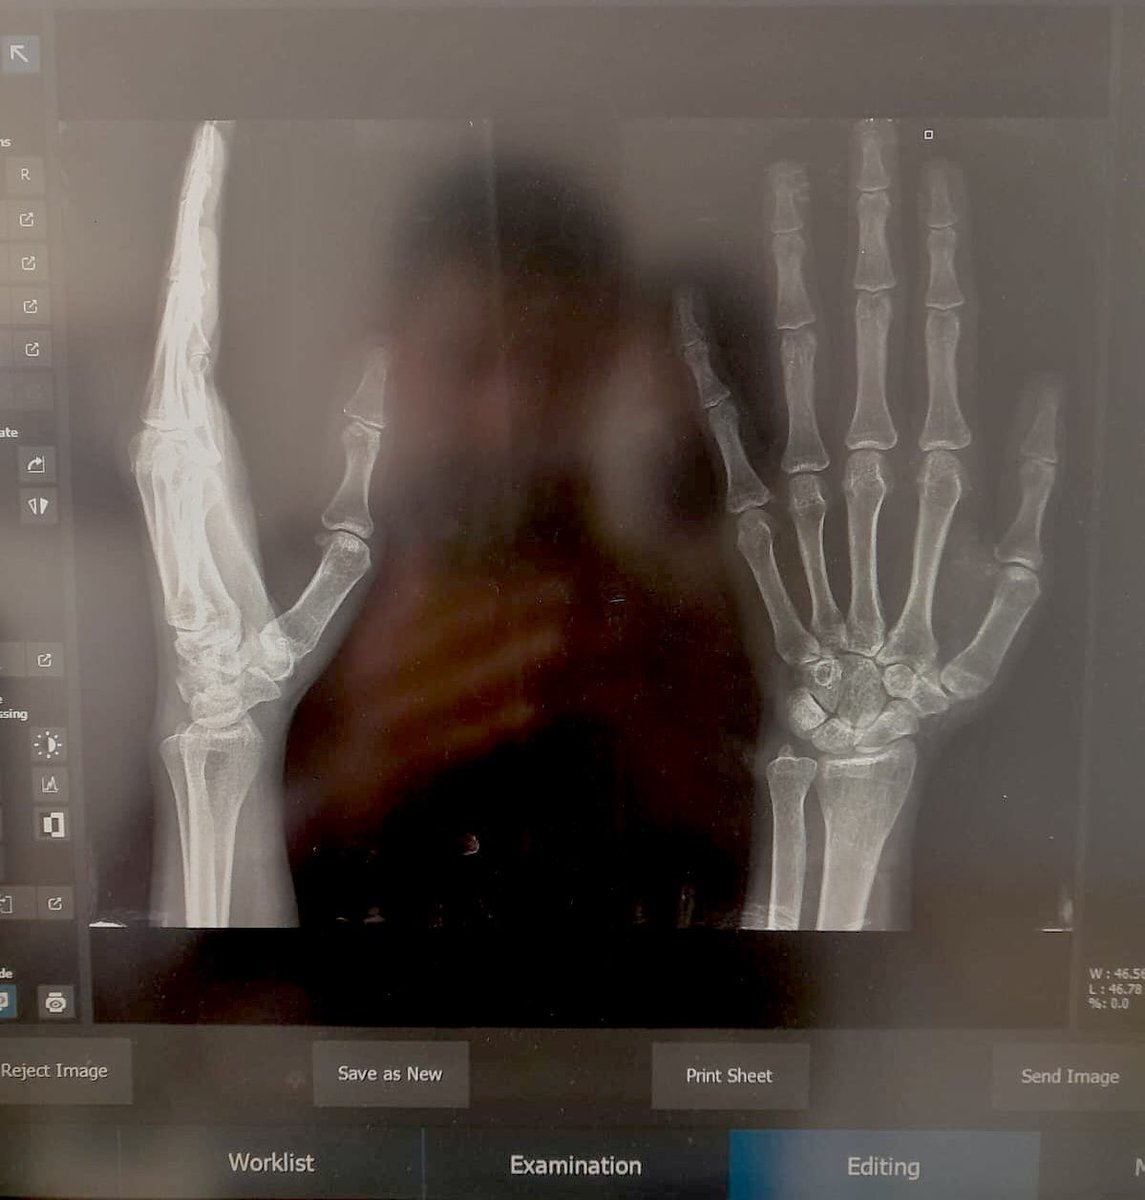

🚨 URGENT MEDICAL REPORT 🚨 I'm Eva from Gaza. I have severe tissue tearing and a displaced joint capsule. The pain is constant & I cannot use my hand at all. I urgently need surgery costing $5,000. Your donation or RT can end my pain. 💔 Donate here 👇 chuffed.org/project/153613